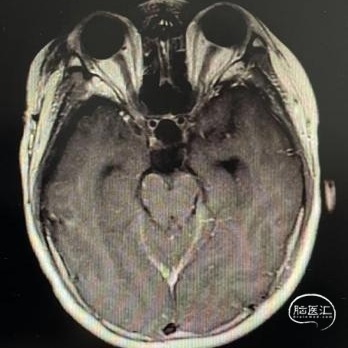

术后MRI

在显微镜下经右侧额下联合终板入路全切除肿瘤,术后视力同术前。

病理检查:造釉细胞型颅咽管瘤伴钙化。